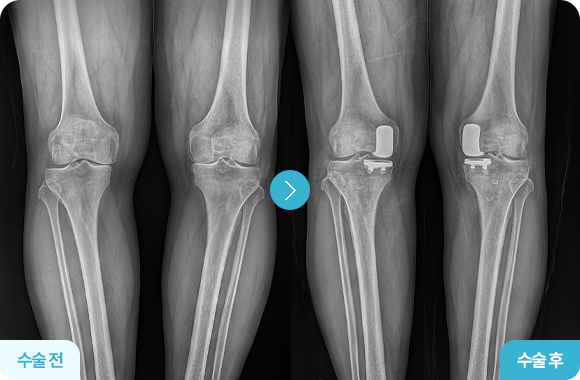

무릎 인공관절 전치환술

무릎 관절의 손상된 연골과 뼈를 모두 제거 후 교체(전체 면적)

퇴행성 관절염이 무릎 전반에 진행된 경우